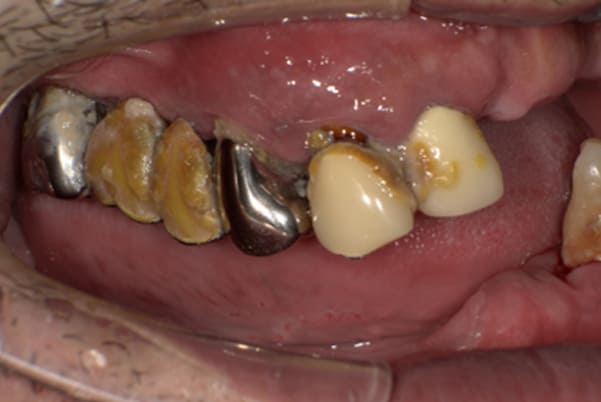

下顎治療前

-

下顎治療後

治療前の入れ歯の奥歯は、治療後の義歯と比較しても分かるように、歯が削れ平らになった状態です。

これにより奥歯のかみ合わせは低くなり、前歯のみが強くあたり、かみ合わせにより上の前歯大きな負担がかかっていたことにより、上の前歯が折れたことが考えられます。